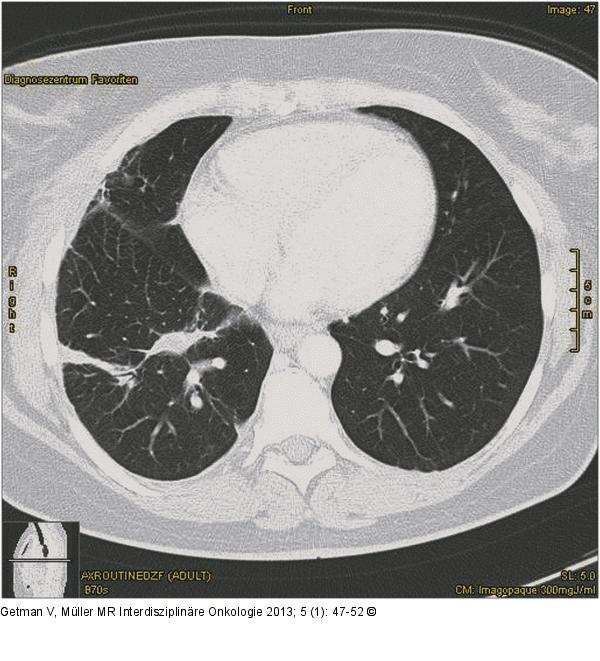

Abbildung 5: CT CT 3 Monate nach Laserentfernung von Metastasen der rechten Lunge. |

CT 3 Monate nach Laserentfernung von Metastasen der rechten Lunge. |